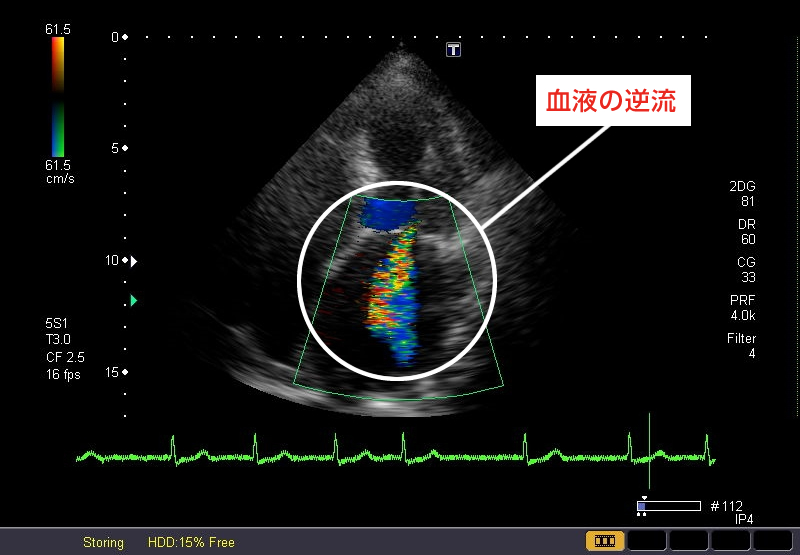

弁膜症

心臓の中には、血液の流れを一方通行にして逆流を防ぐ弁が4つあります。これらの弁の障害による病気が弁膜症です。これには、弁が硬く開きにくくなる「狭窄症」と、弁が閉じきらずに血液が漏れてしまう『閉鎖不全症』があります。弁膜症には、先天性のものや、加齢、動脈硬化などの結果生じるものもあります。

心エコー(超音波)検査

心臓の形や動きに異常がないか弁膜症など血流の乱れがないかなどについて調べます。